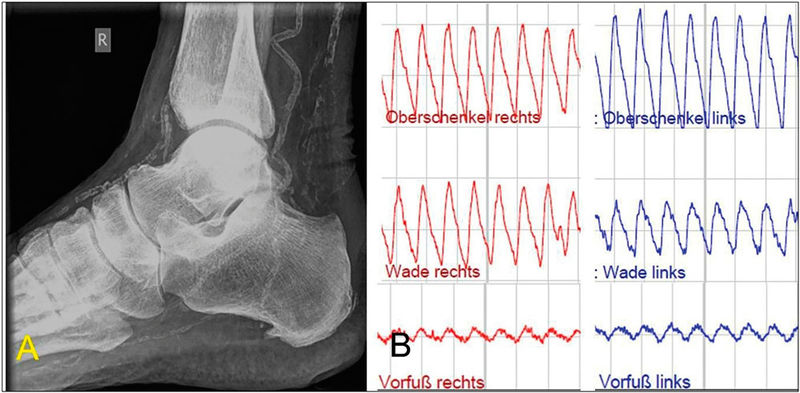

Gemäß Leitlinienempfehlung soll die strukturierte Einschätzung des Amputationsrisikos bei Patienten mit Wunden mit dem „Wound, Ischemia and foot Infection“ (WIfI)-Score vorgenommen werden (Tabelle 2) [1, 6]. Für die Beurteilung der Fußperfusion ist der ABI im vorliegenden Fall aufgrund der diabetischen Mediasklerose nicht aussagekräftig. Eine erweiterte hämodynamische Diagnostik ist erforderlich, zum Beispiel durch Bestimmung der Zehenarteriendruckwerte mit Kalkulation des Zehen-Arm-Index (Toe-Brachial-Index“ (TBI), die segmentale Oszillografie sowie die Analyse der Dopplerfrequenzprofile der Knöchelarterien (Abbildung 2) [7].

Abbildung 2: A: Mediasklerose im Röntgenbild bei einem Patienten mit diabetischem Fußsyndrom, B: Darstellung der reduzierten Vorfußperfusion bei pAVK vom Unterschenkeltyp bds. mittels Oszillografie

Bei unserer Patientin (nicht pulsatiles Vorfußoszillogramm, Zehenarteriendruck 30 mmHg am rechten Fuß) erhärtet sich der Verdacht auf eine kritische Durchblutungsstörung, die in aktuellen Empfehlungen als „critical limb threatening ischemia“ (CLTI) bezeichnet wird [1]. Der WIfI-Score von sechs Punkten prognostiziert ein hohes 1-Jahres-Risiko für eine Majoramputation. Duplexsonografisch zeigt sich die femoropopliteale Achse frei, bei fehlendem Fluss in der A. tibialis anterior und monophasischem Flussprofil in der A. tibialis posterior besteht der V. a. eine pAVK vom Unterschenkeltyp.